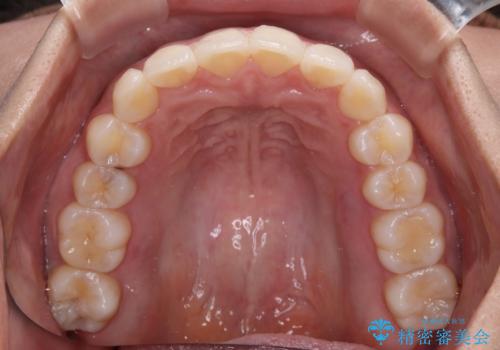

前歯のデコボコを解消 インビザラインの矯正治療

- 前歯のデコボコを治したいとのことで来院された患者様です。

上下顎ともに歯列全体の後方移動とIPR(歯と歯の間を削る)によってデコボコが解消するように設計し、インビザラインにより治療を行うこととしました。